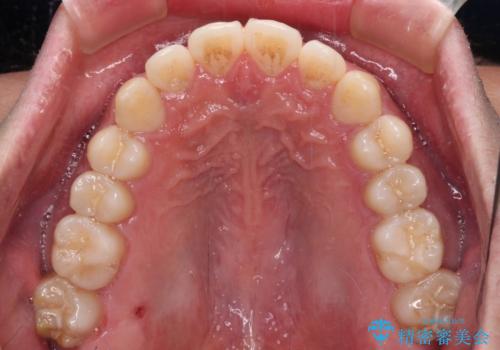

インビザラインで奥歯の咬み合わせと前歯のデコボコを改善

インビザライン単体では右側の交叉咬合を解消することができなかったため、アンカースクリューを併用して咬合を改善させました。